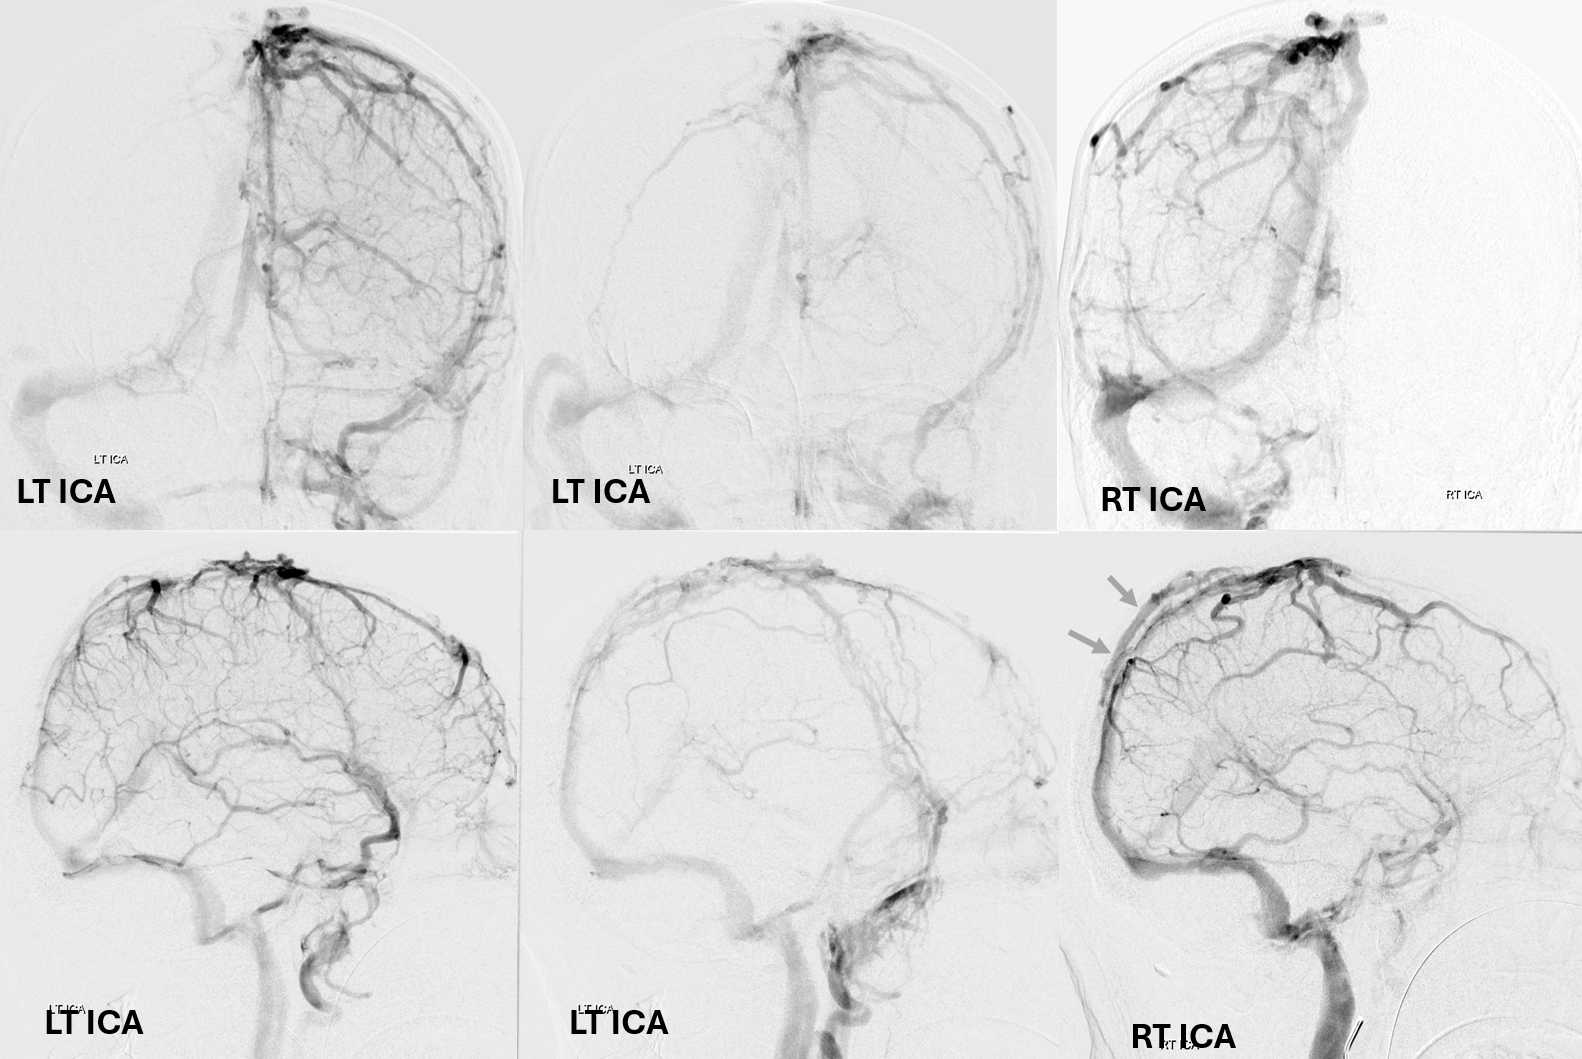

Below is a case of severe venous sinus thrombosis and secondary parenchymal venous infarcts

The explanation for the above tragic pattern is below. On the right, sigmoid and transverse sinuses are patent. However, the Labbe is hypoplastic, and majority of outflow used to go to the Trolard, into the now occluded SSS. There is no other effective way to go — the trolard tries to decompress via a left diploic vein, and convexity tries to access the deep venous system (which normally should not be well-seen in setting of hypoplastic right A1 segment). The left situation is much better, as well-developed superficial sylvian veins drain into the patent Cavernous Sinus. Thus, despite thrombosis of the left transverse and sigmoid sinuses, the left hemisphere is doing better, while the right one, which has patent transverse and sigmoid sinuses, is devastated.

Post venous thrombectomy — with limited results. Note presence of same left diploic vein as seen in right ICA injection, and connection between the distal superior sagittal sinus and the deep venous system via the inferior sagittal sinus.